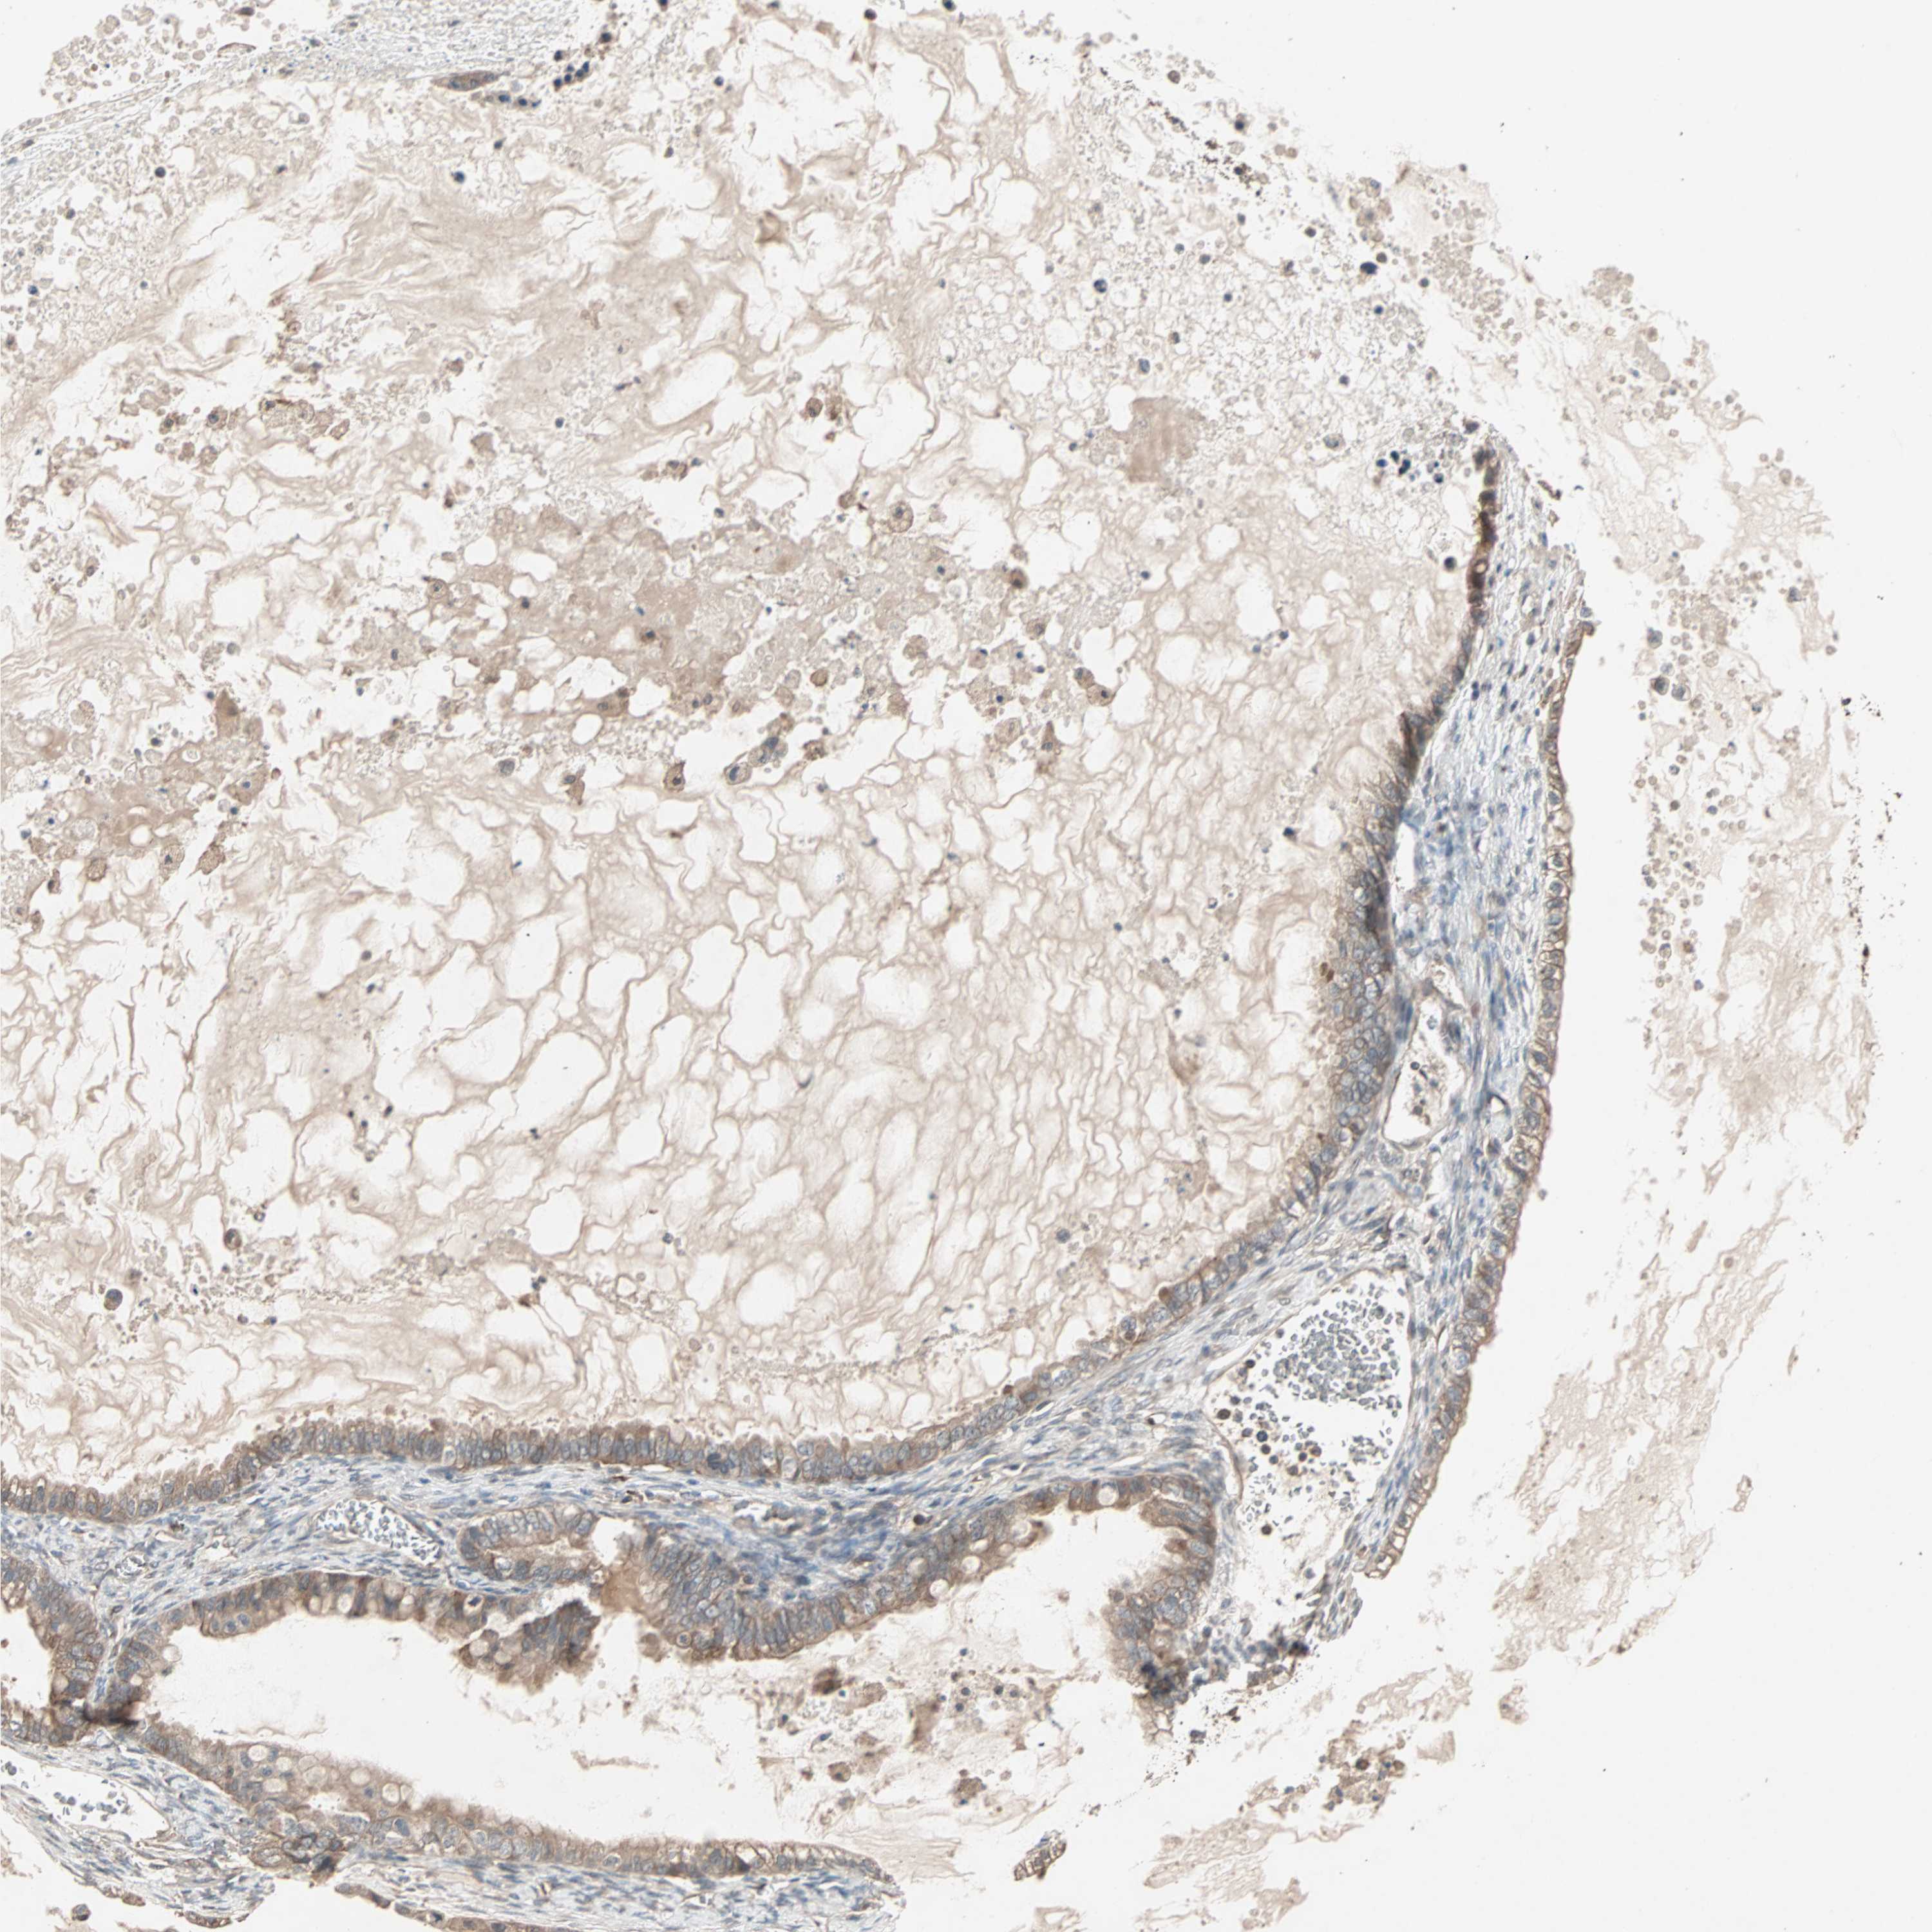

OVARIAN CANCER - Protein expressioni

A mouse-over function shows sample information and annotation data. Click on an image to view it in a full screen mode. Samples can be filtered based on level of antibody staining by selecting one or several of the following categories: high, medium, low and not detected. The assay and annotation is described here.

Note that samples used for immunohistochemistry by the Human Protein Atlas do not correspond to samples in the TCGA dataset.

Antibody stainingi

Antibody staining in the annotated cell types in the current human tissue is reported as not detected, low, medium, or high, based on conventional immunohistochemistry profiling in selected tissues. This score is based on the combination of the staining intensity and fraction of stained cells.

Each image is clickable and will lead to virtual microscopy that enables deeper exploration of all samples and also displays staining intensity scores, fraction scores and subcellular localization as well as patient and tissue information for each sample.

Antibody HPA005651

Staining

High

Medium

Low

Not detected

Intensity

Strong

Moderate

Weak

Negative

Quantity

>75%

75%-25%

<25%

None

Location

Nuclear

Cytoplasmic/membranous

Cytoplasmic/membranous,nuclear

Cystadenocarcinoma, serous, NOS

Carcinoma, endometroid

Cystadenocarcinoma, mucinous, NOS

Carcinoma, NOS